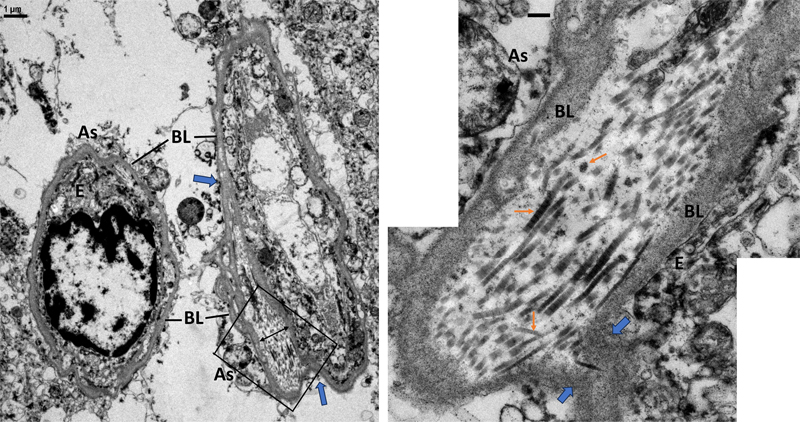

Fig 4. 38-year-old male with amyotrophic lateral sclerosis. Spinal cord. Immunohistochemistry of collagen type I, III, and IV (Col 1, Col 3, Col 4) in serial sections of the same field near central canal epithelium (arrowheads). Note some of Col 4-stained microvessels are also stained with Col 3 and Col 1 (arrows). In the large vessels, Col 4 outlines the vessel and the endothelial basal lamina, while Col 1 and Col 3 stained the media that normally contains fibrillar collagens surrounding vascular smooth muscle cells. Scale bar, 50 μm. As would be expected, IHC of Col 4 showed immunostaining of many microvessels in various cerebral regions, cerebellar vermis and spinal cord as Col 4 is the major BL component. Importantly, in all cases, many of the same vessels in serial sections were also immunostained strongly for Col 3 and weakly for Col 1. EM (Figs 5–13) and IEM (Figs 14–22) confirmed the IHC findings of microvessels. Cross sections of capillaries were selected to ensure their proper orientation for measurement of diameter and their ultrastructural organization. Like capillaries in non-CNS regions of the human body, CNS capillaries have luminal endothelium and abluminal BL with pericytes embedded within the BL. The BL were composed of a homogeneous structure representing the fused BL of endothelial cell/pericyte and perivascular astrocyte. Also observed were segments with apparent splitting of the BL (Fig 5). Some of the split BL were shown to be continuous with fused BL in the same section. The most striking finding was the small to large amounts of fibrils deposited in various focally expanded spaces bounded by split BL. These fibrils displayed characteristic banding patterns of fibrillar collagens, with a width ranging from 50–80 nm diameter. Sometimes, collagens larger than 120 nm were found (Fig 8, Supplementary Fig 32). All fibrils appeared randomly oriented in the expanded space. Very sparse cytoplasmic elements were present in the expanded space. Tissues from short PMI autopsies and biopsies showed pericapillary parenchyma tightly wrapping the capillaries, even in areas with massive, banded collagen deposits (Fig 10, Supplementary Figs 26, 41, 57). No banded fibrils were observed outside of the BL. No phagocytotic cells or inflammatory cells were present. There was minimal astrogliosis, and despite autolytic changes, astroglial processes maintained hemi-desmosome attachments on fused or split BL (Fig 20–22, Supplementary Figs 55) [52]. There was no evidence of extensive BL remodeling (e.g., duplication or thickening) of either fused or split BL.

Fig 5. 9-year-old male with tauopathy, neurofilament inclusion disease, motor neuron disease. Cingulate. Top. Electron micrograph of a capillary at low magnification showing fused basal lamina (BL) of endothelial cell (E) and perivascular astrocyte (As) at the top and bottom, and split BL at the left and right side of the capillary. Arrowheads point to split of fused BL. RBC, red blood cell in capillary lumen. Bottom. Enlargements of boxed areas showing expanded spaces [double head arrows] in the split BL contain bundles of banded fibrils in cross, oblique and longitudinal sections [arrows]. Scale bars, top, 1μm; bottom, 0.2μm.

Fig 6. 18-year-old male with no significant brain pathology. Superior frontal cortex. Postmortem interval, 18 hours. Same case with IHC depicted in figure 2. Left. Electron micrograph of two capillaries with homogenous fused basal lamina (BL) of endothelial cell (E) and perivascular astrocyte (As). Note the right capillary has an expanded space [double head arrow] formed by split BL (arrowheads). Right. Enlargement of boxed area shows the expanded space containing many banded fibrils (arrows) in random orientation. Arrowheads indicate splits of the two BLs. Scale bar, right, 0.2μm.